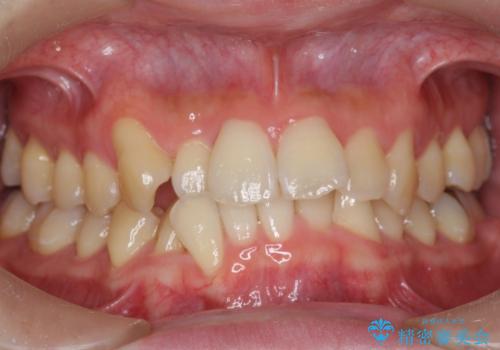

ねじれ・がたつきのある前歯を改善

- がたつき・すれ違い、ねじれのある前歯の見た目、噛み合わせの改善を希望され来院されました。

4本の小臼歯抜歯を避け、下顎前歯の1本抜歯の極力少ない抜歯本数で審美的な歯並びを得る治療計画としました。

見た目の改善だけでなく、噛みやすくなったことにも満足いただくことができました。